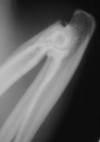

11

Q

A

Monteggia fractures